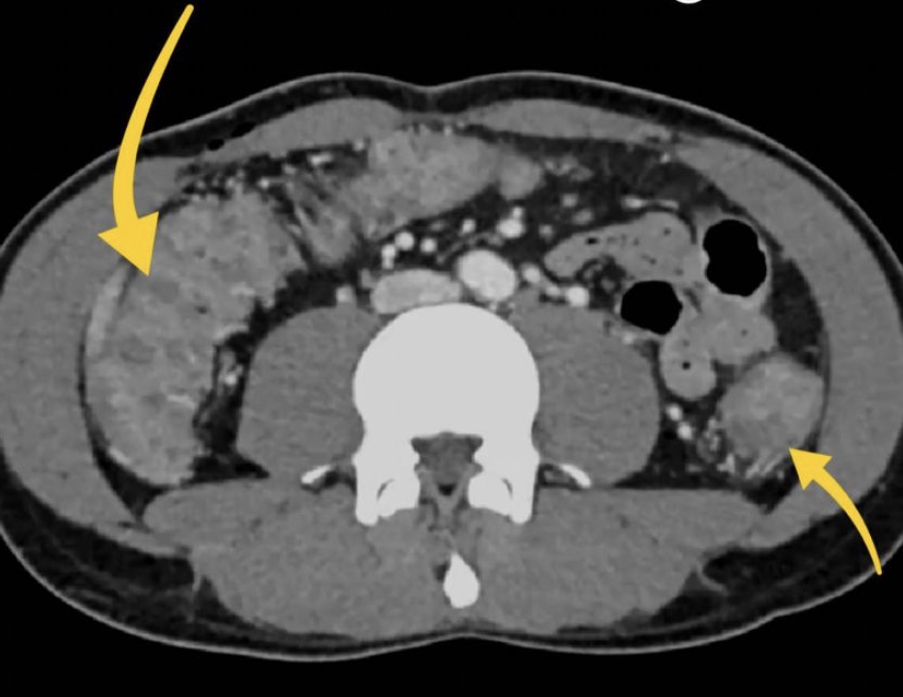

Due to pain the patient could only tolerate a few STIR sequences so we don’t have a complete scan but have a look at this axial STIR sequence below. We have high STIR signal within the right psoas with locules suggesting abscess formation.

Have a look at this axial STIR image from the MRI scan. Here we have high SITR signal within the right psoas with locules suggesting abscess formation.